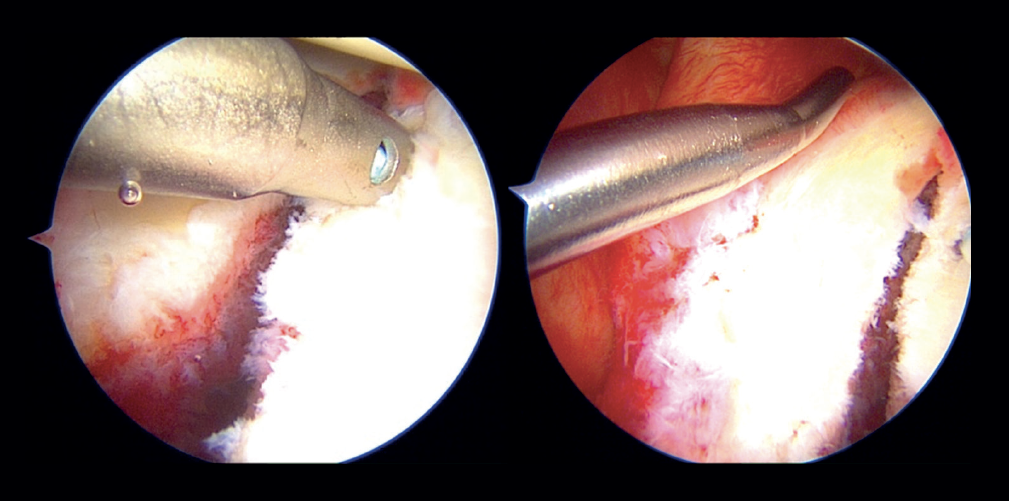

In the classical Porcellini-Sugaya technique, debridement and roughening of the bone margins of the fracture was carried out with synoviotome, rasps and curettes (Figure 2). All-suture anchorings were used for the repair. The first anchoring was placed in the lowermost zone of the defect (Figure 3), and one its extremities extended to the damaged labrum in the lowermost zone, followed by knotting. The second anchoring was placed in the uppermost zone of the defect (Figure 4), in the same way as the first, followed by knotting. In those cases where considered necessary, one or two more anchorings were added proximal to the previous ones. Reduction and stability of the fragment was checked.